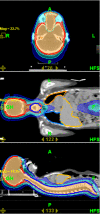

Mean coverage index for entire group of patients and all PTVs was 0,82 ± 0,13. Mean homogeneity index was 1,07 ± 0,02. Mean PTV doses, coverage and homogeneity indexes for selected challenging cases or groups of patients are presented in Table 3. Even for challenging cases of craniospinal irradiation and extended thoracic and abdominal volumes irradiation coverage and homogeneity of delivered dose were acceptable. Mean doses for selected OARs are presented in Table 4. It shows that substantial sparing of critical structures was achieved in all patients although major variability in OARs mean doses in this very heterogeneous patient population is evident. In Figures 2 and 3 examples of treatment plan for medulloblastoma and perineal rhabdomyosarcoma with metastases to inguinal nodes are presented.

Figure 2 Thumb

Figure 2. Dose distribution for craniospinal irradiation.

Click image to view larger.

Figure 3 Thumb

Figure 3. Dose distribution for perineal rhabdomyosarcoma.